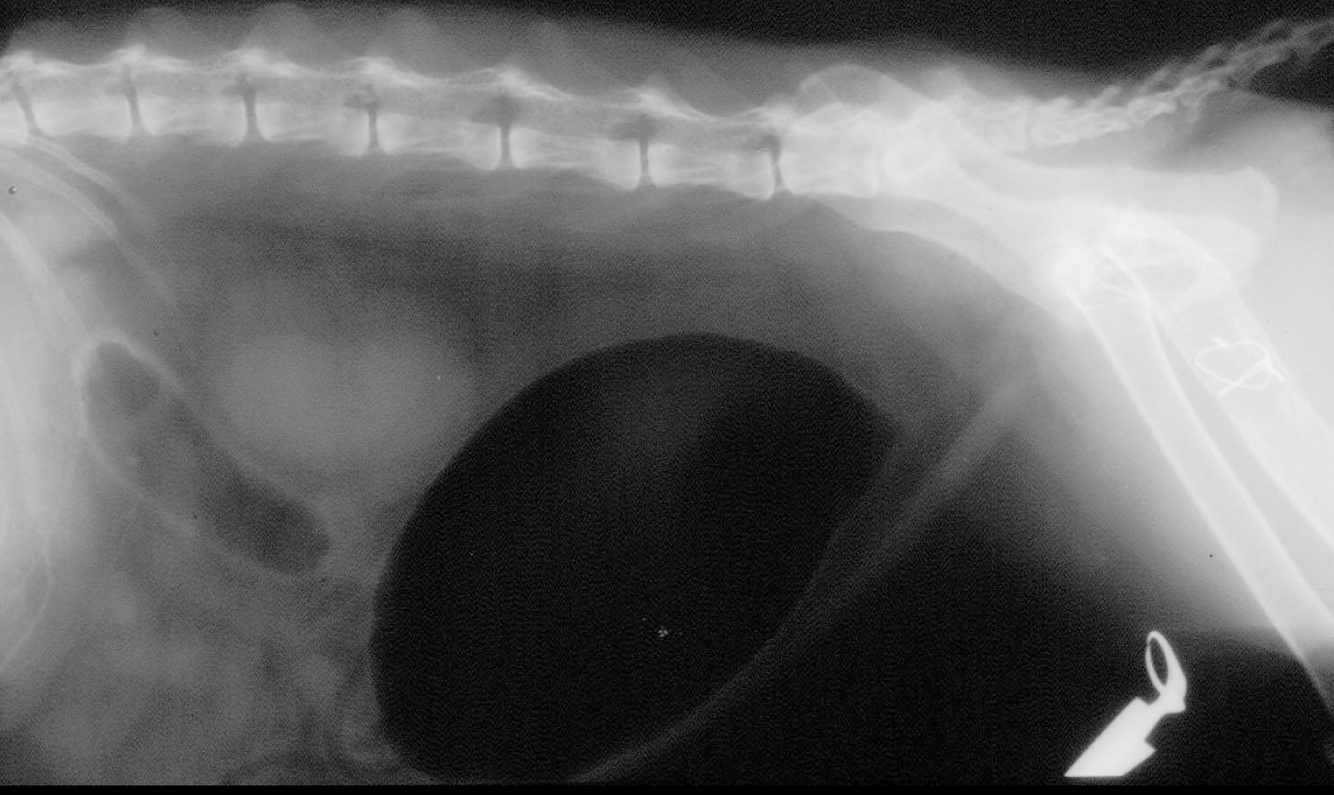

What is seen in this cystourethrograph?

A

negative gas contrast only